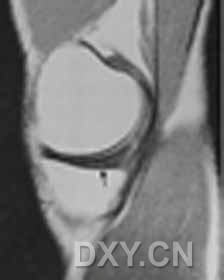

| 0级 外侧半月板表现为均匀低信号,形态规则